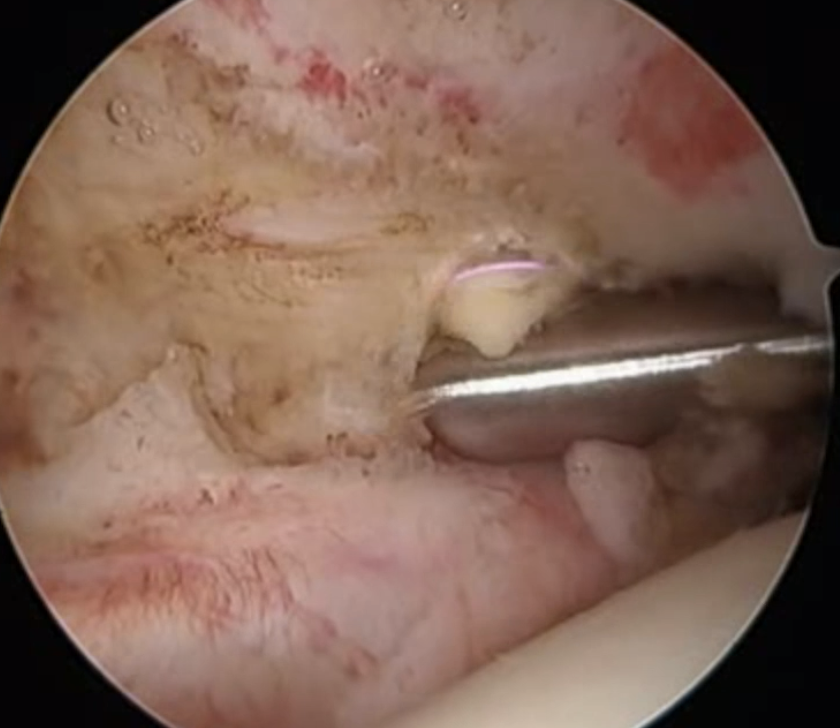

Full thickness tear of subscapularis off insertion revealed with grasper

Comma Sign

Comma sign

- medially retracted subscapularis tear

- exposes the superior insertion of superior glenohumeral ligament / coracohumeral ligament

Full thickness retracted subscapularis tear with comma sign

Full thickness completely retracted subscapularis, loss of rotator interval and comma sign

Full thickness completely retracted subscapularis, loss of rotator interval and comma sign